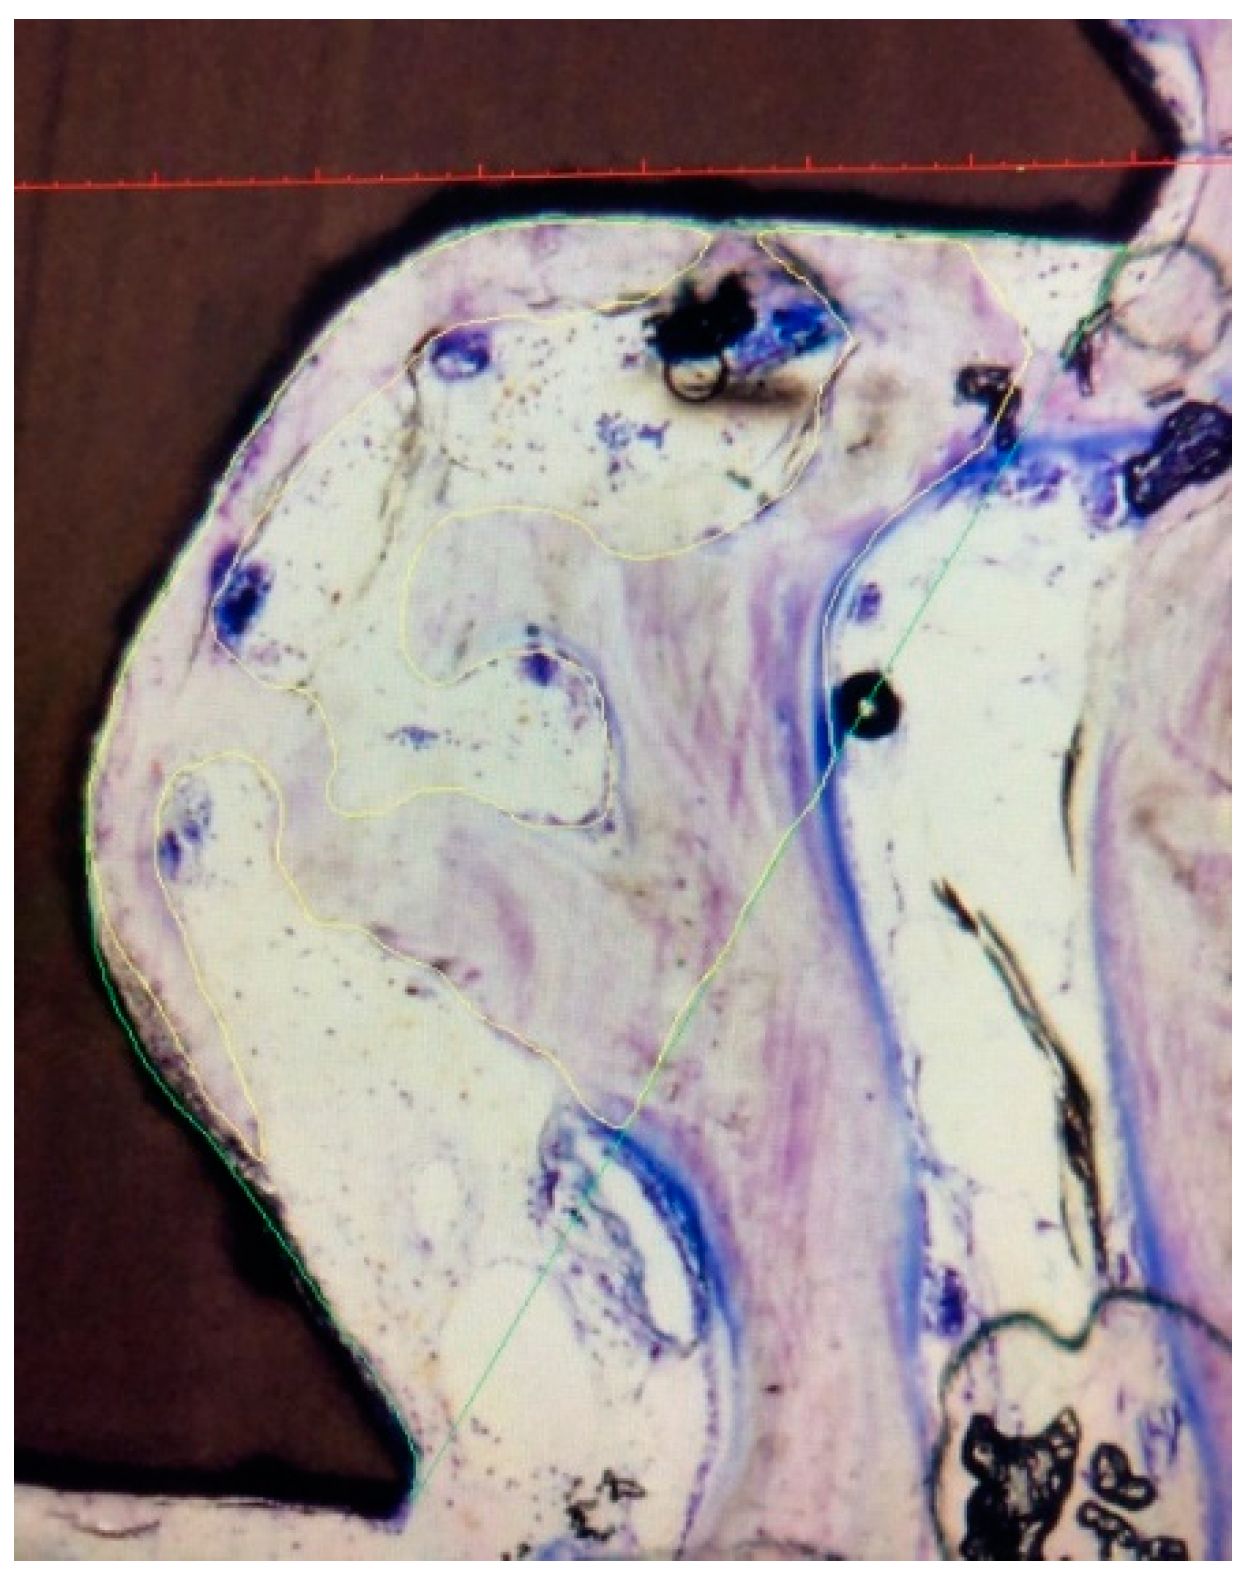

2.5. Histomorphometrical Preparation and Analysis

3.1. Scanning Electron Microscopy

3.4. Histomorphometrical Evaluation